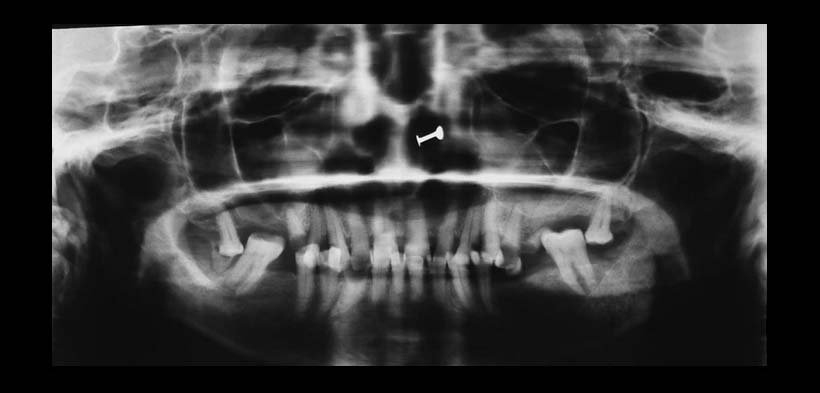

Fig. 1. Radiografía panorámica de una paciente con diagnóstico de mieloma múltiple. Se muestra un aspecto de rayos de sol de la región parasinfisiaria del lado izquierdo.